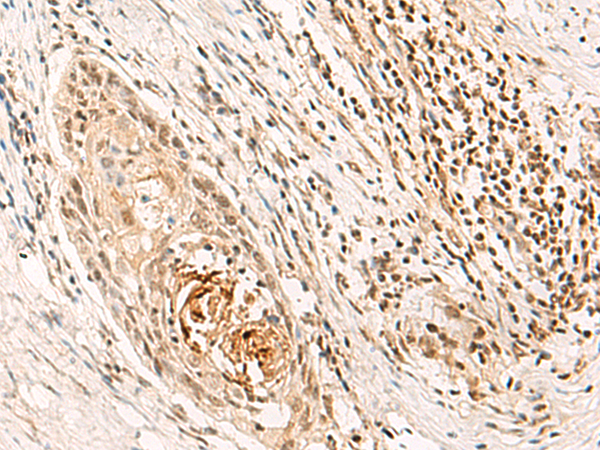

分类: 科研抗体货号: P05820别名:应用: WB,IHC反应种属: Human, Mouse, Rat